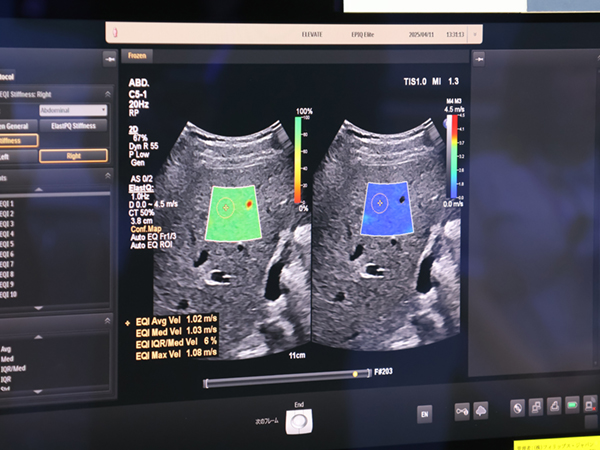

超音波診断装置は,4月1日に販売を開始した「EPIQ Elite/Affiniti」の最新バージョンとなる「Elevate」シリーズが実機を使ったデモンストレーションで紹介された。検査者に依存しやすい超音波検査の質を均質化・向上するための自動化機能や高度なアルゴリズムが搭載されている。自動画像調節ツール「AutoSCAN Assistant」は,ピクセル単位の最適化アルゴリズムや深さ方向の自動輝度調整により,手動調整の手間を減らし,患者ごとに最適化した画像をリアルタイムに描出する。また,肝臓エラストグラフィの「Auto ElastQ」は,従来はマニュアルで行っていたフレーム選択と,データの信頼度を表すConfidence Mapを見ながらのROI設定,計測を自動化。1つの動画から最適な3フレームが選択され,ROI設定,計測が自動で行われることで,検査者間のバラツキを抑え,検査時間を最大60%短縮する。

肝臓エラストグラフィのフレーム選択から計測までを自動化する「Auto ElastQ」